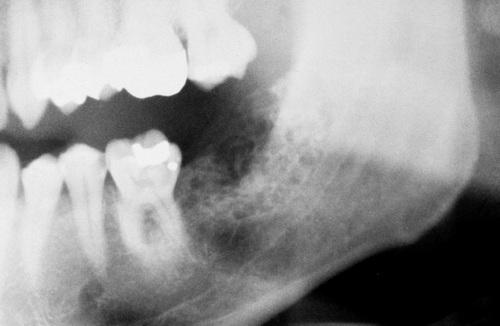

This large, multilocular cyst involves most of the ascending ramus and is growing in an anteroposterior direction.

odontogenic keratocyst (OKC)

This cyst involves the crown of an unerupted premolar, which appears similar to a dentigerous cyst.